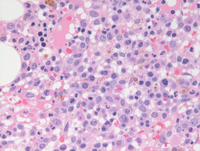

Bone marrow biopsy findings-higher power

Bone marrow biopsy at higher power demonstrates the mononuclear cells with evidence of dispersed chromatin compatible with blasts in the first two images. Paratrabecular clusters of blastic cells around the bone are also noted. The last image demonstrates a single dysplastic hypolobated megakaryocytes in the center of the field.